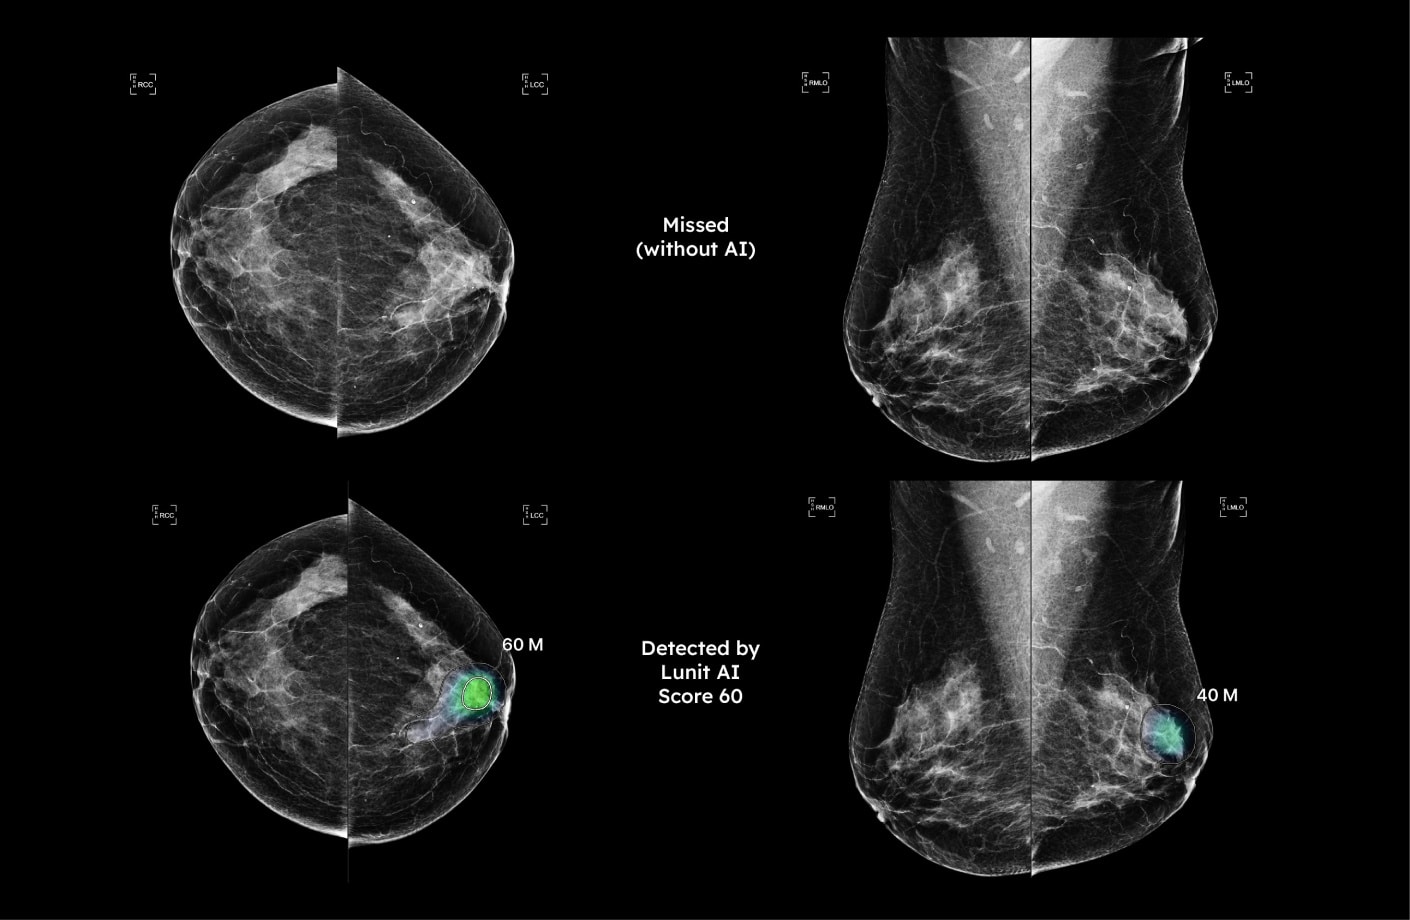

O Lunit INSIGHT MMG oferece uma valiosa assistência aos radiologistas ao contribuir para o aumento da produtividade e atuar como suporte de suas interpretações. O software recebe as imagens feitas pelo mamógrafo e as processa pelo seu mecanismo de investigação, que identifica e classifica áreas suspeitas de câncer de mama a serem revisadas elos médicos.

Além disso, o resultado da análise permite visualizar e estimar, quantitativamente, a probabilidade da presença de células cancerígenas. As regiões que se destacam pela possível malignidade são marcadas pelo mapa de cores ou de tons de cinza com pontuação de anormalidade (%), o que reflete a chance da presença do tumor. A partir dos escores gerados pela IA, os radiologistas podem triar até 100% dos casos.